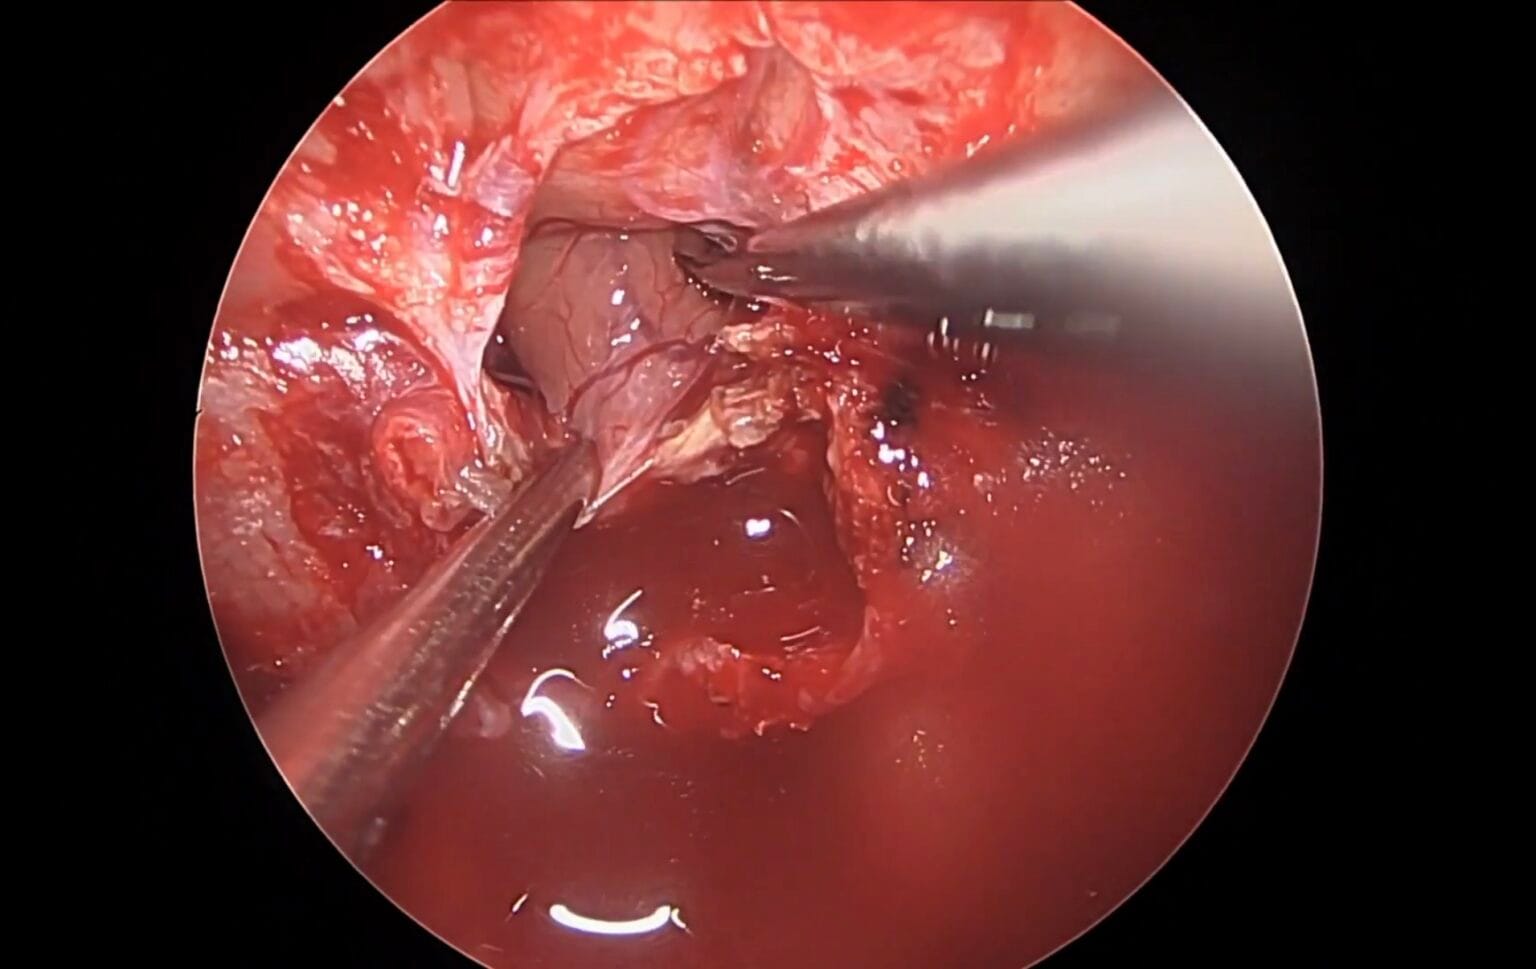

Resección microquirúrgica de un craneofaringioma retroquiasmático

El Dr. Luis Borba realiza la resección microquirúrgica de un craneofaringioma retroquiasmático mediante abordaje petroso posterior modificado

Clipaje transcavernoso de aneurisma de la ACS

Se presenta un caso de clipaje de un aneurisma de la arteria cerebelosa superior con un tratamiento previo con flow-diverter fallido.